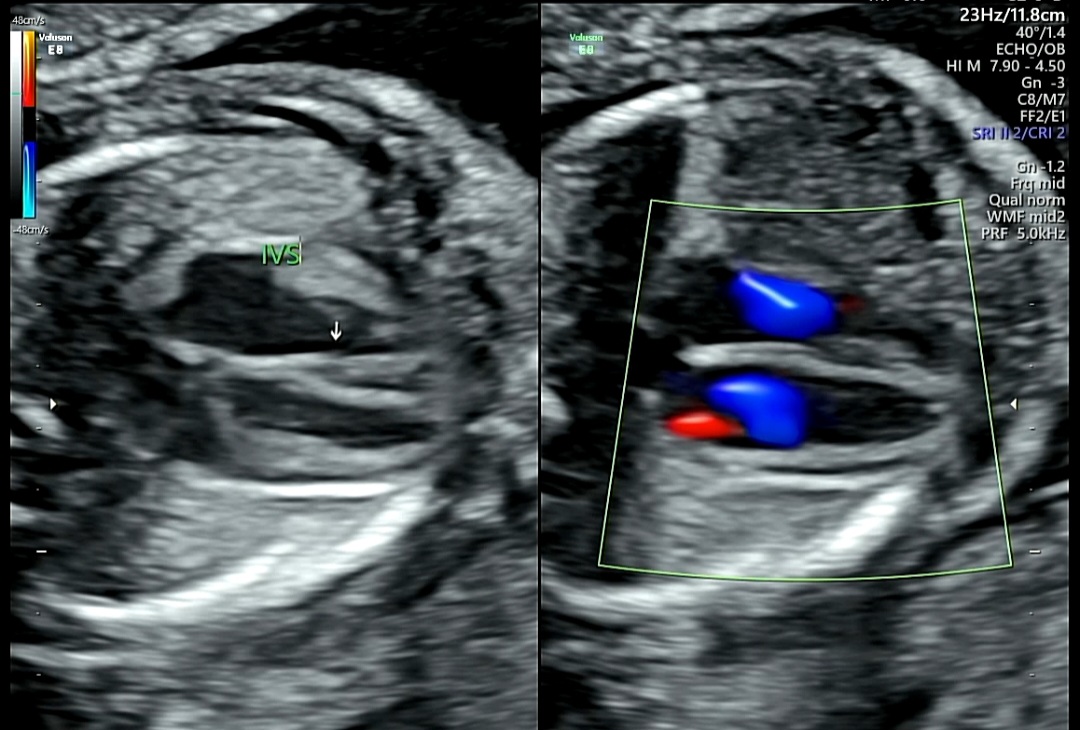

2. 심장 구조 확인 (4CV,3V, IVS, A-A, LV OT, RV OT)

1) 4CV (Four Chamber View, 4심방 단면)

심장의 4개 방(좌·우심방, 좌·우심실) 이 한눈에 보이는 장면

→ 좌우 크기가 균형 있고 벽이 잘 구분되면 정상

2) 3V (Three Vessel View, 3혈관 단면)

심장에서 나오는 세 가지 주요 혈관(폐동맥, 대동맥, 상대정맥)을 함께 보는 단면

→ 세 혈관이 일정한 크기로 잘 배열되어 있다면 정상 혈관 구조

3) IVS (Interventricular Septum, 심실중격)

IVS : 좌심실과 우심실 사이 벽(중격)을 뜻함

→ 이 부분에 구멍이 있으면 심실중격결손(VSD)이라고 하는데,

위 사진처럼 중격이 잘 보이고 화살표로 표시된 부분에 단절 없이 이어져 있다면 정상